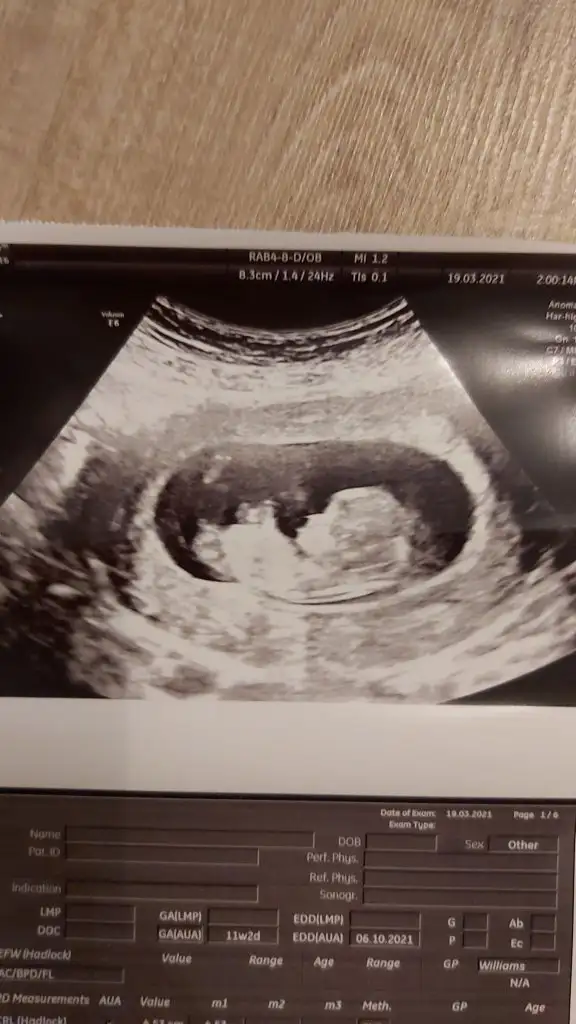

Merhaba. Rica etsem benim usmya tahmin yapar mısınız?

12+2 günlüktü burda. Karından detaylı ultrasondu.

Doktor benzetme yaptı ama kesin değil dedi.doktorla aynı olursa oyumu veririm